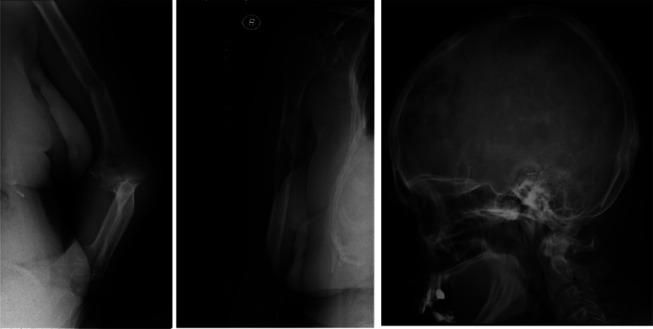

When "Myeloma" is not a Myeloma: a case report of malignant bone lymphoma.

Abstract Image